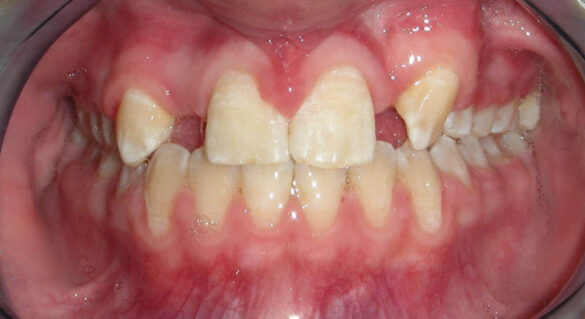

La momentul prezentării în clinică, în decembrie 2002, pacienta avea 8 ani şi o lună şi suferea de fibroză chistică şi de o deficienţă de dezvoltare a etajului mijlociu al feţei. Aceasta prezenta o anomalie de clasa I care mima o anomalie de clasa a III-a. Incisivii centrali, laterali şi caninii temporari maxilari, precum şi molarii prim şi secund de pe partea stângă erau în ocluzie inversă. În plus, pacienta prezenta coloraţii ale dinţilor de etiologie idiopatică (fig. 1). Autorii au considerat coloraţiile ca fiind de suprafaţă, extrinsece şi nu determinate de fibroza chistică, dovadă îndepărtarea acestora prin periaj profesional. Radiografia panoramică efectuată cu 6 luni înainte de prezentarea în clinica stomatologică relevă anodonţia incisivilor laterali superiori şi a premolarului secund drept inferior, ca şi posibila incluzie a caninilor maxilari, în special a celui stâng (fig. 2).